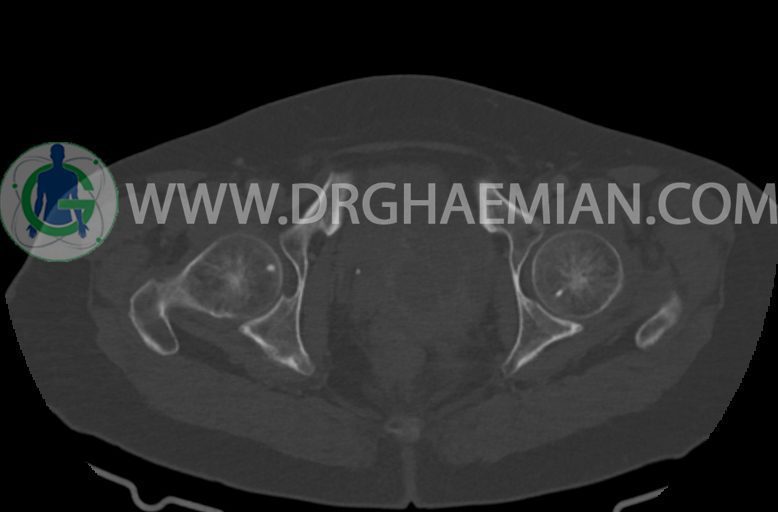

–ساختار Cystic multiseptate همراه با Enhancing thick septation به ابعاد 79x62mm در

لگن دیده می شود که در درجه اول مطرح کننده ی ضایعات نئوپلاستیک تخمدانی نظیر mucinous cyst adenocarcinoma است.

–ضایعه ی mass like هیپردنس- هتروژن به قطر 42mm در سمت راست لگن